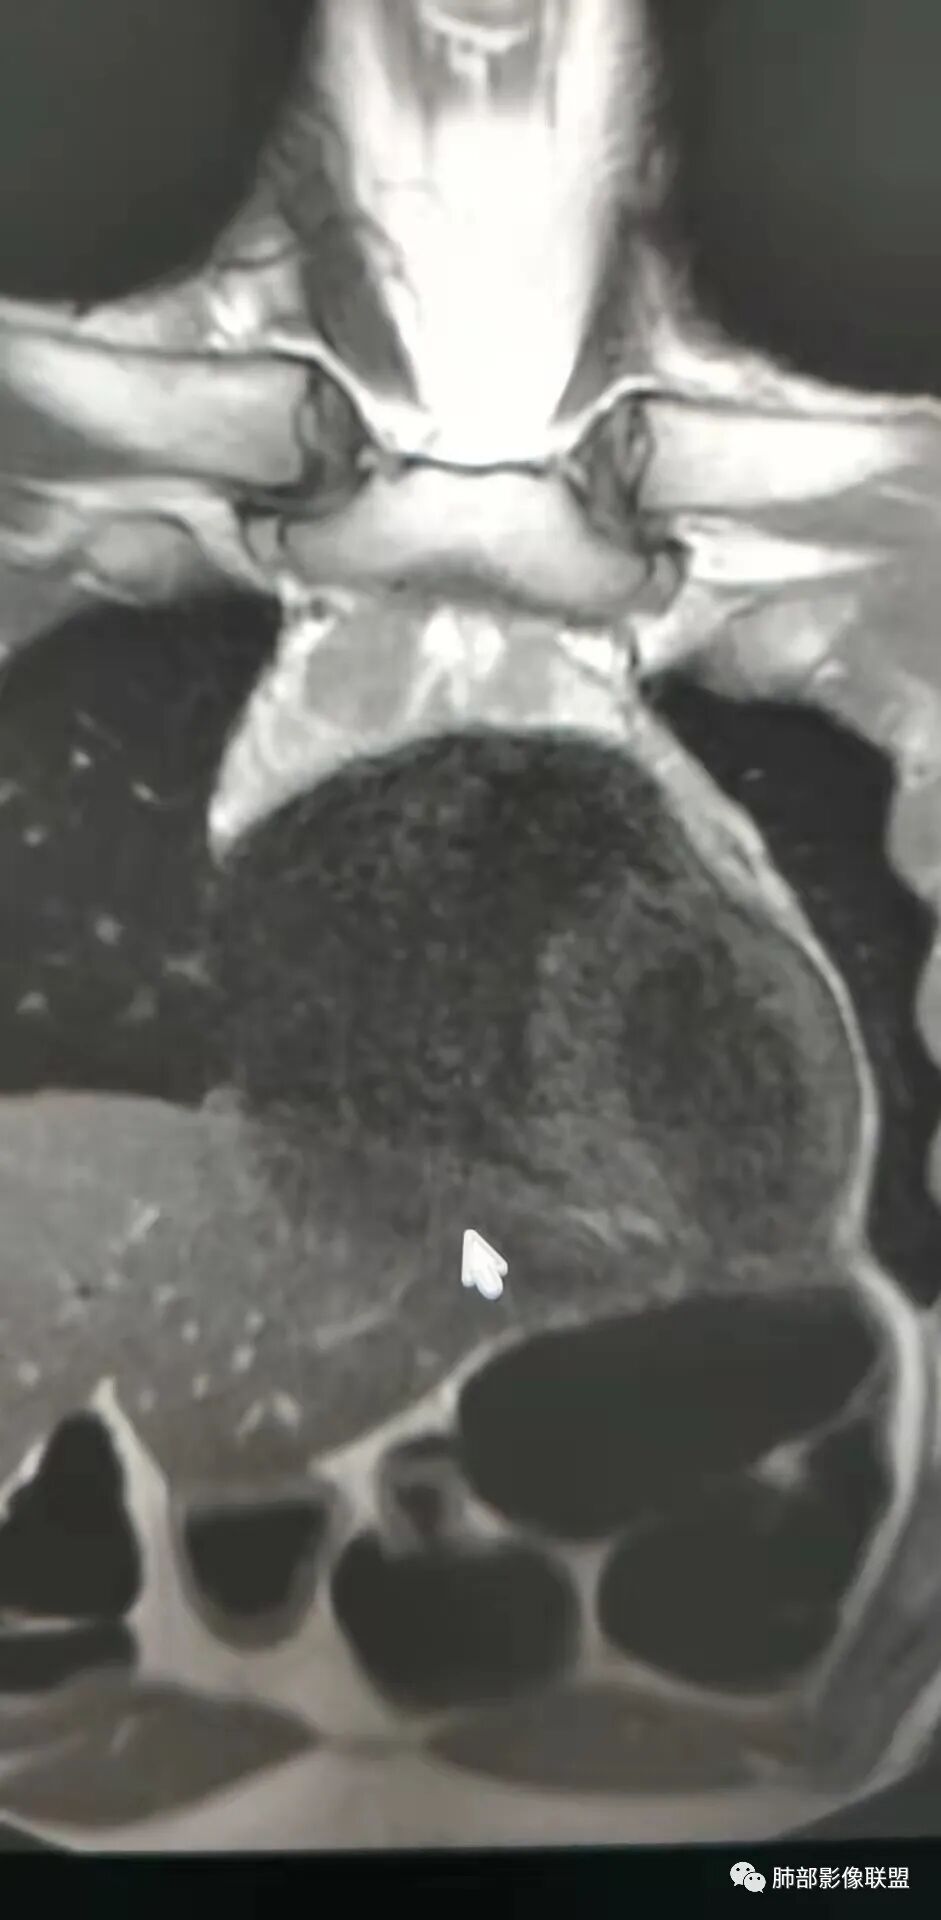

看看这个内部结构

但是结构疏松,边界不清:

问题是不是都是结节状,部分是条带状

胸腺内的

多发病灶

从MR看结构松散

不太符合肿瘤

首先考虑非肿瘤性病变

炎症?

增生?

炎症:符合点——强化、周围边界不清,白介素6高,但是没症状,DWI中央低强化区不高

增生:符合点——整体内部结构松散,不符合点强化,白介素6高

关键在于其结构松散,外周密度增高,周围渗出

整体形态没有肿瘤的特点,特别是MR

就觉得内部结构松散

无肿瘤的特点